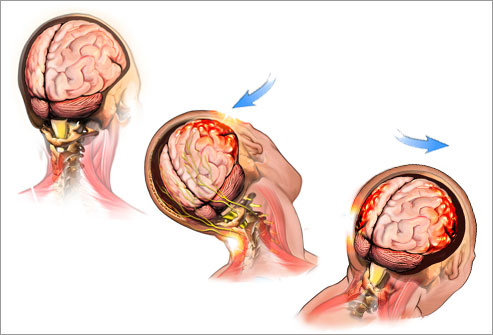

A concussion is the most common type of closed brain injury and is classified as a mild traumatic brain injury (mTBI). Concussions occur when a blow, bump, or sudden movement causes the brain to move rapidly inside the skull, temporarily affecting how the brain functions.

In the past, concussions were often identified only when someone lost consciousness or could not remember the event. Today, we know that many concussions occur without loss of consciousness, and symptoms may develop immediately or hours later.